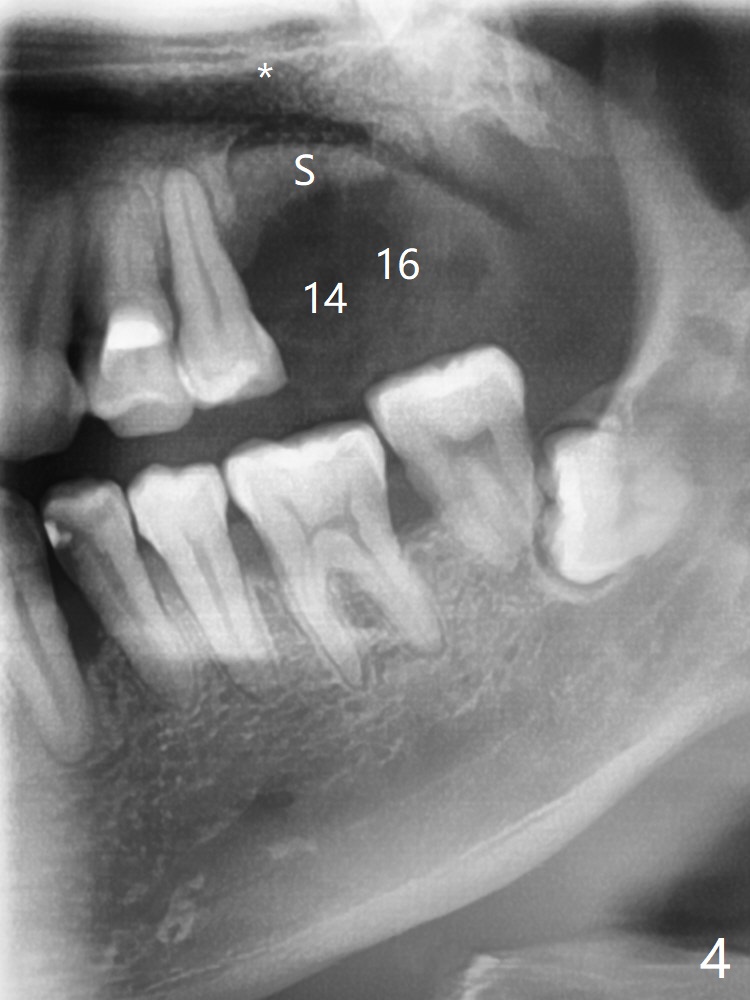

47岁男原本回诊所拔除近中左上智齿(16号牙),影响第一磨牙(14号牙)植牙周围炎治疗后卫生维护。事先制备PRF(图一,二)和骨块(图三 *),拔牙顺利,发现植牙螺纹依然暴露,决定取出植体,上颌窦底板缺失,但膜仿佛完整,放置一小块PRF于上颌窦底,促进上颌窦膜愈合,然后加入新的骨粉,与剩余上清液(图三 >)调袢,虽然不再形成粘性骨块,但是还有好处,放置于拔牙窝以及植牙窝(图四 *),浅部放置骨块(S),这样骨粉不容易丢失,表面再放置PRF膜和不可吸收膜(Cytoplast),使用PTFE缝线。术后7周Cytoplast几乎完全暴露(图五)。当它取出后,骨粉好像损失不少(图六)。二个月后再评价。术后6.5月第一磨牙区仍萎缩(图七),只好再植骨,在第三磨牙区安置一个tenting screw,也在第一磨牙区植入第二个钉子,但是不牢靠,因为仍处于纤维状,把它往上颌窦推作为上颌窦粘膜(图八:>),然后提升(*)。在第一,第三磨牙交界处打入第二个帐篷钉,在两个钉子周围放置粘性骨粉,覆盖PRF膜,缝合。估计植骨效果不佳,植牙时再植骨。